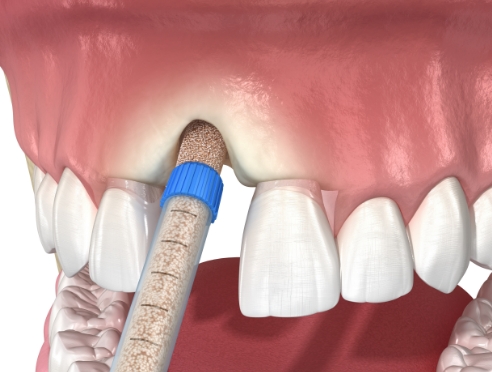

通过CT, 扫描等数字设

备拍摄后,

进行精密分析

考虑骨骼状态与神经位置,

制定种植位置与手术计划

根据患者状况,

应用个性化种植牙设计

按照预定导板,

稳定植入种植牙